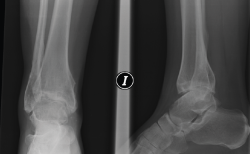

Figura 8. Caso de la Figura 6 a los 3 años de la distracción articulada. Obsérvese el mantenimiento del espacio articular a nivel de la articulación del tobillo.